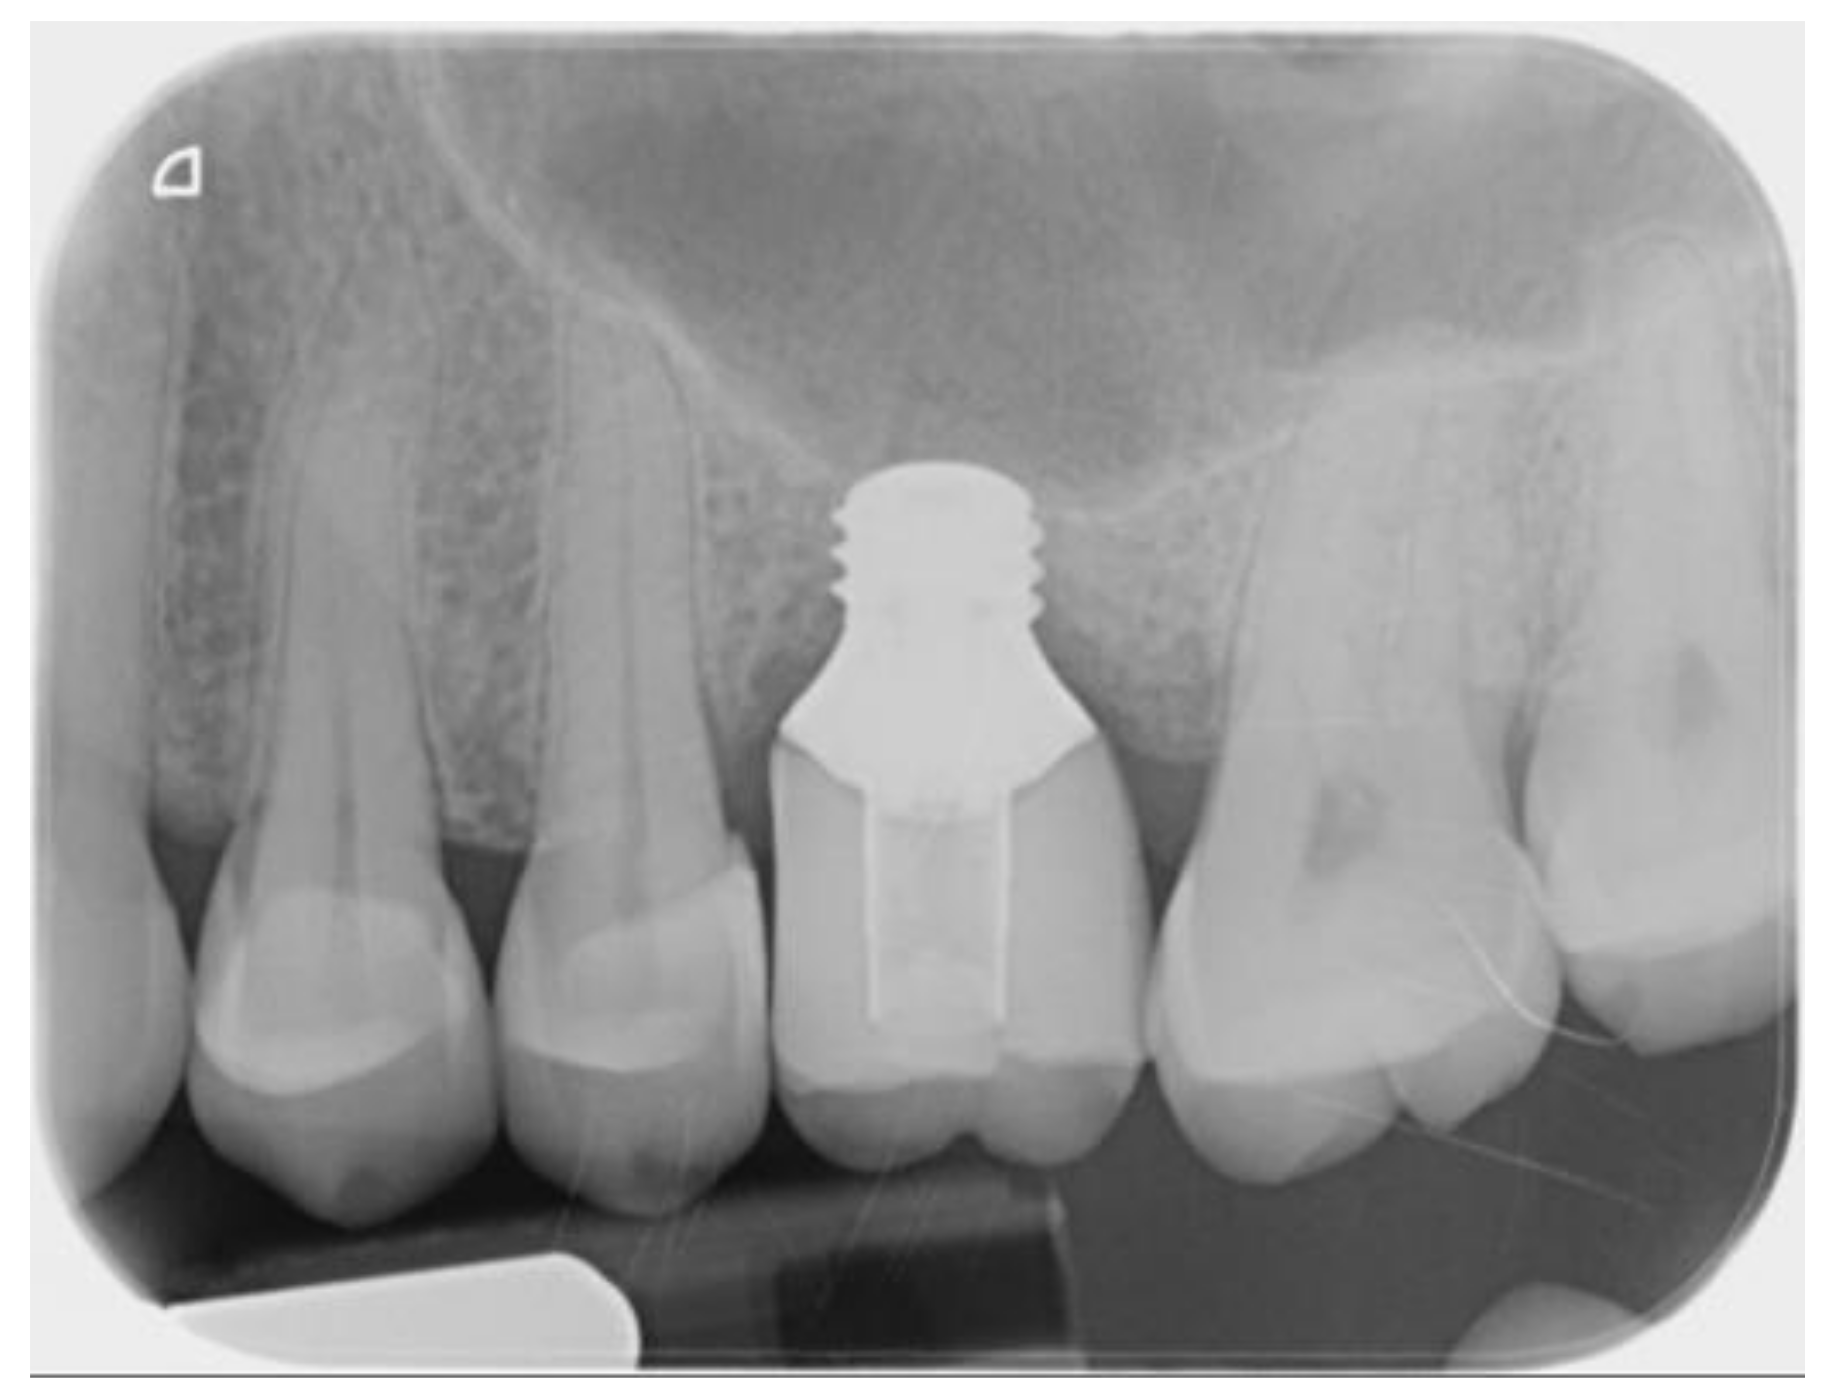

2.2. Surgical and Prosthetic Procedure

3. Results